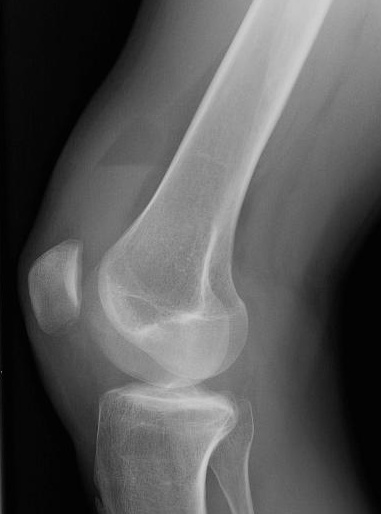

KNEE - LATERAL RADIOGRAPH

This standing lateral view of the right knee demonstrates the distension of the suprapatellar recess by a lipohemarthrosis.